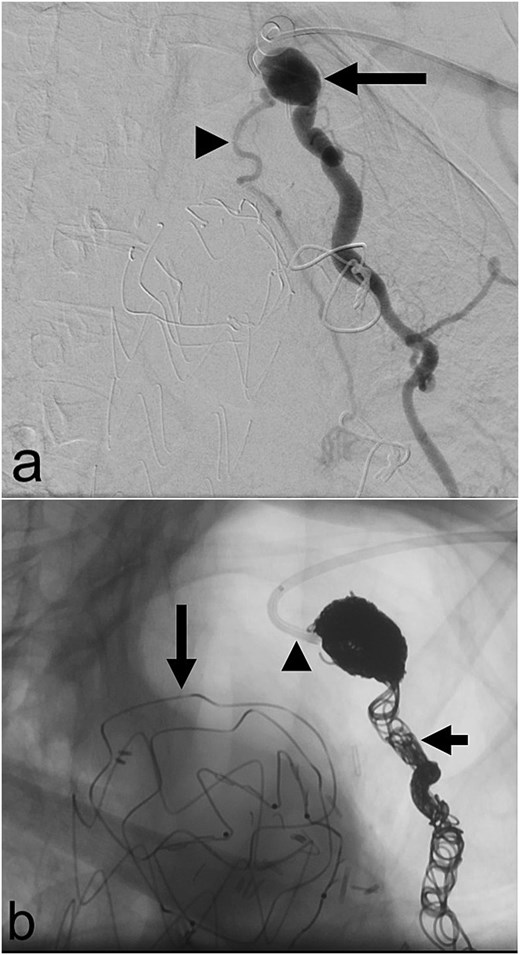

In May 2023, she underwent coil embolization of an aneurysmal proximal left internal mammary artery (LIMA) giving rise to a bronchial collateral that was felt to be feeding the LUL lesion (Fig. 2). The collateral could not be subselectively catheterized. There was short-term resolution of her symptoms after which they recurred.

(a) Aneurysmal left internal mammary artery (arrow) with bronchial collateral (arrowhead) on digital subtraction angiography; (b) selective catheterization of the origin of the left internal mammary artery (arrowhead) via a left radial arterial approach with coil embolization of the left internal mammary artery (short arrow) and a thoracic aortic endograft (long arrow) on fluoroscopy.